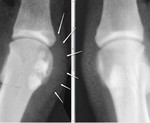

На рентгенограмме может выявиться, что сесамовидная кость состоит из двух или более отдельных костей, как будто это перелом, но границы между ними гладкие. Это нормально и может наблюдаться у каждого десятого. На рентгенограмме оценивается положение сесамовидных косточек, а также пространство (сочленение) между головкой плюсневой кости и сесамовидными костями. Суставное пространство в норме на рентгенограмме выглядит равномерным. Сужение и неравномерность говорит о патологии.

У меня есть претензии к медиальной сесамовидной косточке слева - подозрение на асептический некроз. хотя, не исключаю, что ее фрагментация есть всего лишь анатомической особенностью.

Правая стопа отснята для сравнения.

Коллеги, сесамовидные кости - тибиальная и фибулярная, а не медиальная и алтеральная, насколько я помню анатомию. В данном случае желателен рентген другой стопы для оценки бипартиты, а так - сесамоидит/стресс перелом.

Да. спасибо, действительно, рентген второй стопы есть. Значит, скорее всего стресс-перелом.